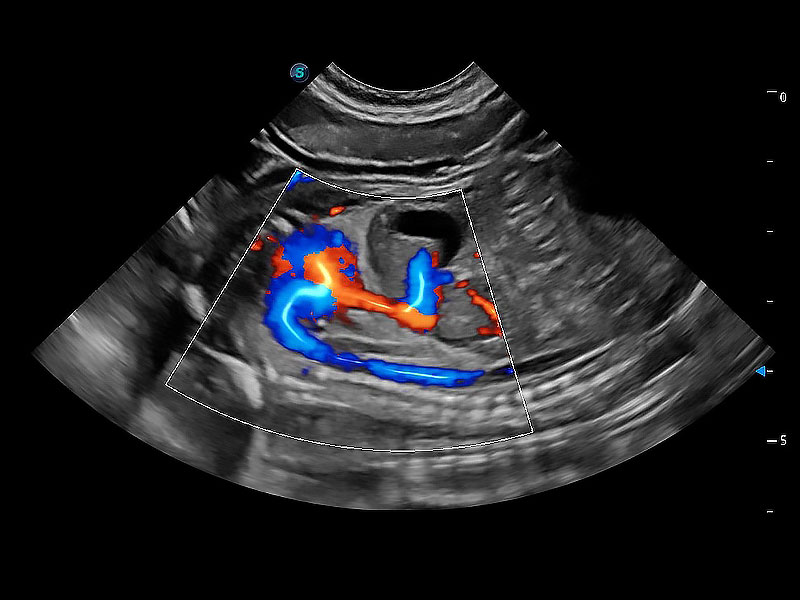

極大提升超低速微細(xì)血流的檢出能力,同時更精準(zhǔn)地濾除軟組織和超聲信號,為獸用醫(yī)生提供以往無法通過常規(guī)血流獲得的疾病診斷信息。

在傳統(tǒng)二維血流成像的基礎(chǔ)上,呈現(xiàn)血流的立體感,具有動感的生命力之美。即便是微小的血管也能輕松應(yīng)對,提高了血流的視覺敏感性。

非線性融合造影成像充分利用諧波和基波信號,為難以觀察的血流進(jìn)行增強(qiáng)顯像??捎糜诰€陣、凸陣、微凸陣、相控陣探頭。